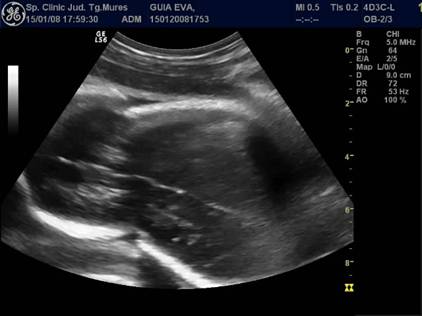

Fig nr. 240.

Edem tegumentar al coapsei ( sageata ) aparut la maceratie, aceeasi sarcina ca

in figurile anterioare